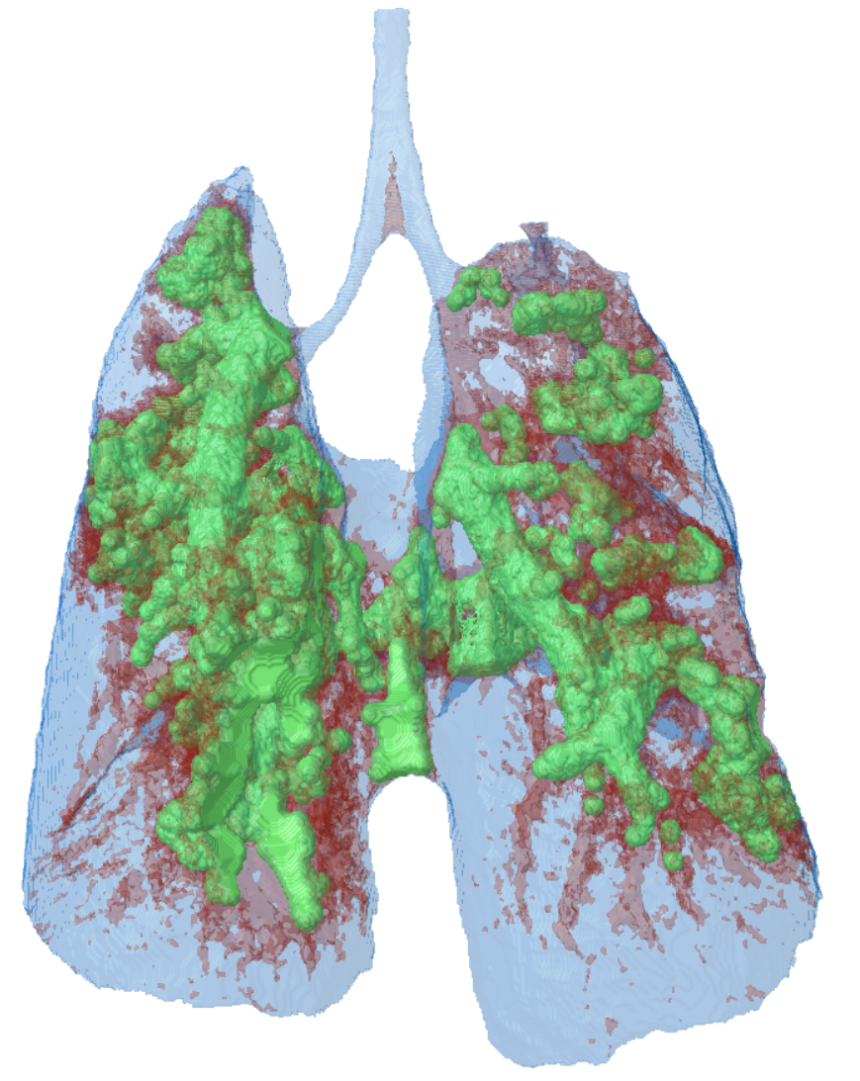

Pneumology

The SKYSCAN 1278 is a versatile lung imaging solution for both mouse and rat. Rat lungs are imaged in a single scan FOV thanks to the large and fast cMOS flat panel x-ray camera. The scanner and accompanying software provide sharply time-gated lung images in short scan times with safe levels of ionizing radiation. As with all SKYSCAN in vivo scanners, physiological monitoring is integrated at the heart of the instrument, with the welfare of the scanned animal the top priority.

- Comprehensive time-gating solutions: prospective and retrospective, time and image based intrinsic gating. Continuous rotation available for fast low-dose gated scanning.

- Full in-house software solution for lung function analysis in 4D: tidal volume, lung volume and HU density for pathology assessment, lung tumor morphometric segmentation, 3D registration of sequential scans to map disease progression, auto-separation of lung from other animal tissues in CT-Analyser software.